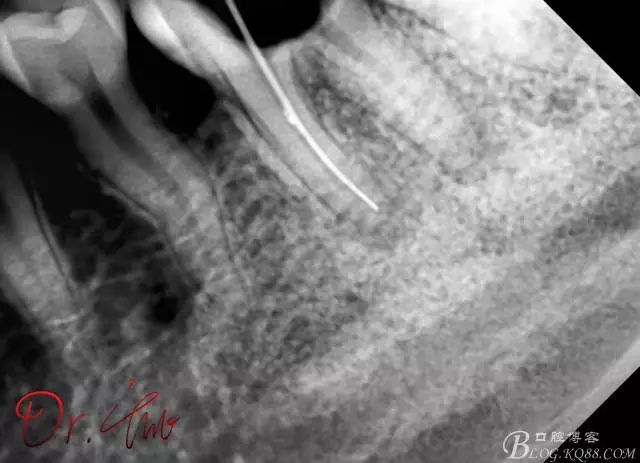

重點(diǎn)第二例病例,初診

640.webp (5).jpg

拍片確定長(zhǎng)度

640.webp (6).jpg

試主尖,近中頰側(cè)形成臺(tái)階

640.webp (7).jpg

試主尖,近中頰側(cè)再次拍片查看臺(tái)階位置及確定長(zhǎng)度

640.webp (8).jpg